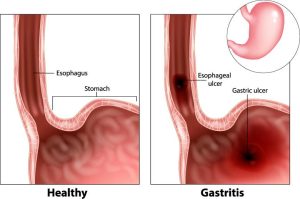

Chronic gastritis

Chronic gastritis is a chronic inflammation of the mucosal lining of the stomach. According to the histological changes of the gastric mucosa, the disease can be divided into superficial, atrophic or hypertrophic gastritis.

Chronic gastritis is a chronic inflammation of the mucosal lining of the stomach. According to the histological changes of the gastric mucosa, the disease can be divided into superficial, atrophic or hypertrophic gastritis.The actual cause of chronic gastritis is not known. It may have connection with bad dietary habits, certain foods (excessive consumption of alcohol, cigarettes, strong tea and coffee), taking certain drugs for a long period of time, bile regurgitation, stress or immune dysfunction.

Different types of chronic gastritis have different clinical manifestations. The symptoms of superficial gastritis include stomach upset after meals, then feeling comfortable after hiccups. Sometimes the patient also feels sick, vomits and experiences acid reflux as well as stomach ache, but shows no prominent signs. The main symptoms of atrophic gastritis include loss of appetite, feeling pain in the upper abdomen, suffering from anaemia and diarrhoea, becoming thinner and feeling tired. As for hypertrophic gastritis, the main symptom is stubborn pain in the upper abdomen. Food and alkaline medication can relieve the pain, which has no special rhythm.

As this disease has no specific symptoms and signs, gastroscope and biopsy of the gastritis mucosa are the major methods in diagnosing the disease.

Peptic ulcer

Peptic ulcer is a common disease of the alimentary tract. Ulceration occurs mostly in the stomach and duodenum. Therefore, the term peptic ulcer covers both stomach ulcers and duodenal ulcers.

Peptic ulcer is a common disease of the alimentary tract. Ulceration occurs mostly in the stomach and duodenum. Therefore, the term peptic ulcer covers both stomach ulcers and duodenal ulcers.Peptic ulcer presents mainly as cyclic pain. The pain from a gastric ulcer comes on half an hour to two hours after a meal, localised at the epigastrium, in the midline or to the left. Duodenal ulcer presents pain 3 to 4 hours after eating, or during the night, relieved by food or use of antacid. The location of pain is in the upper abdomen in the midline or to the right. Other symptoms peptic ulcer can include nausea, vomiting, heartburn, burping, indigestion, distension of the upper abdomen and anaemia. In some cases, peptic ulcers may be asymptomatic and then present as an acute episode of bleeding or perforation. Diagnosis of a peptic ulcer can be ascertained by barium meal swallow or gastroscopy.

HeliiResearch has now shown that most of the peptic ulcers occur as a result of infection by a bacterium known as Helicobacter pylori (H. pylori). Other risk factors include taking non-steroidal anti-inflammatory drugs (NSAIDs, e.g. aspirin and ibuprofen). Lifestyle factors such as stress, irregular diet, alcohol, caffeine and smoking also play a part in the development of ulcers.